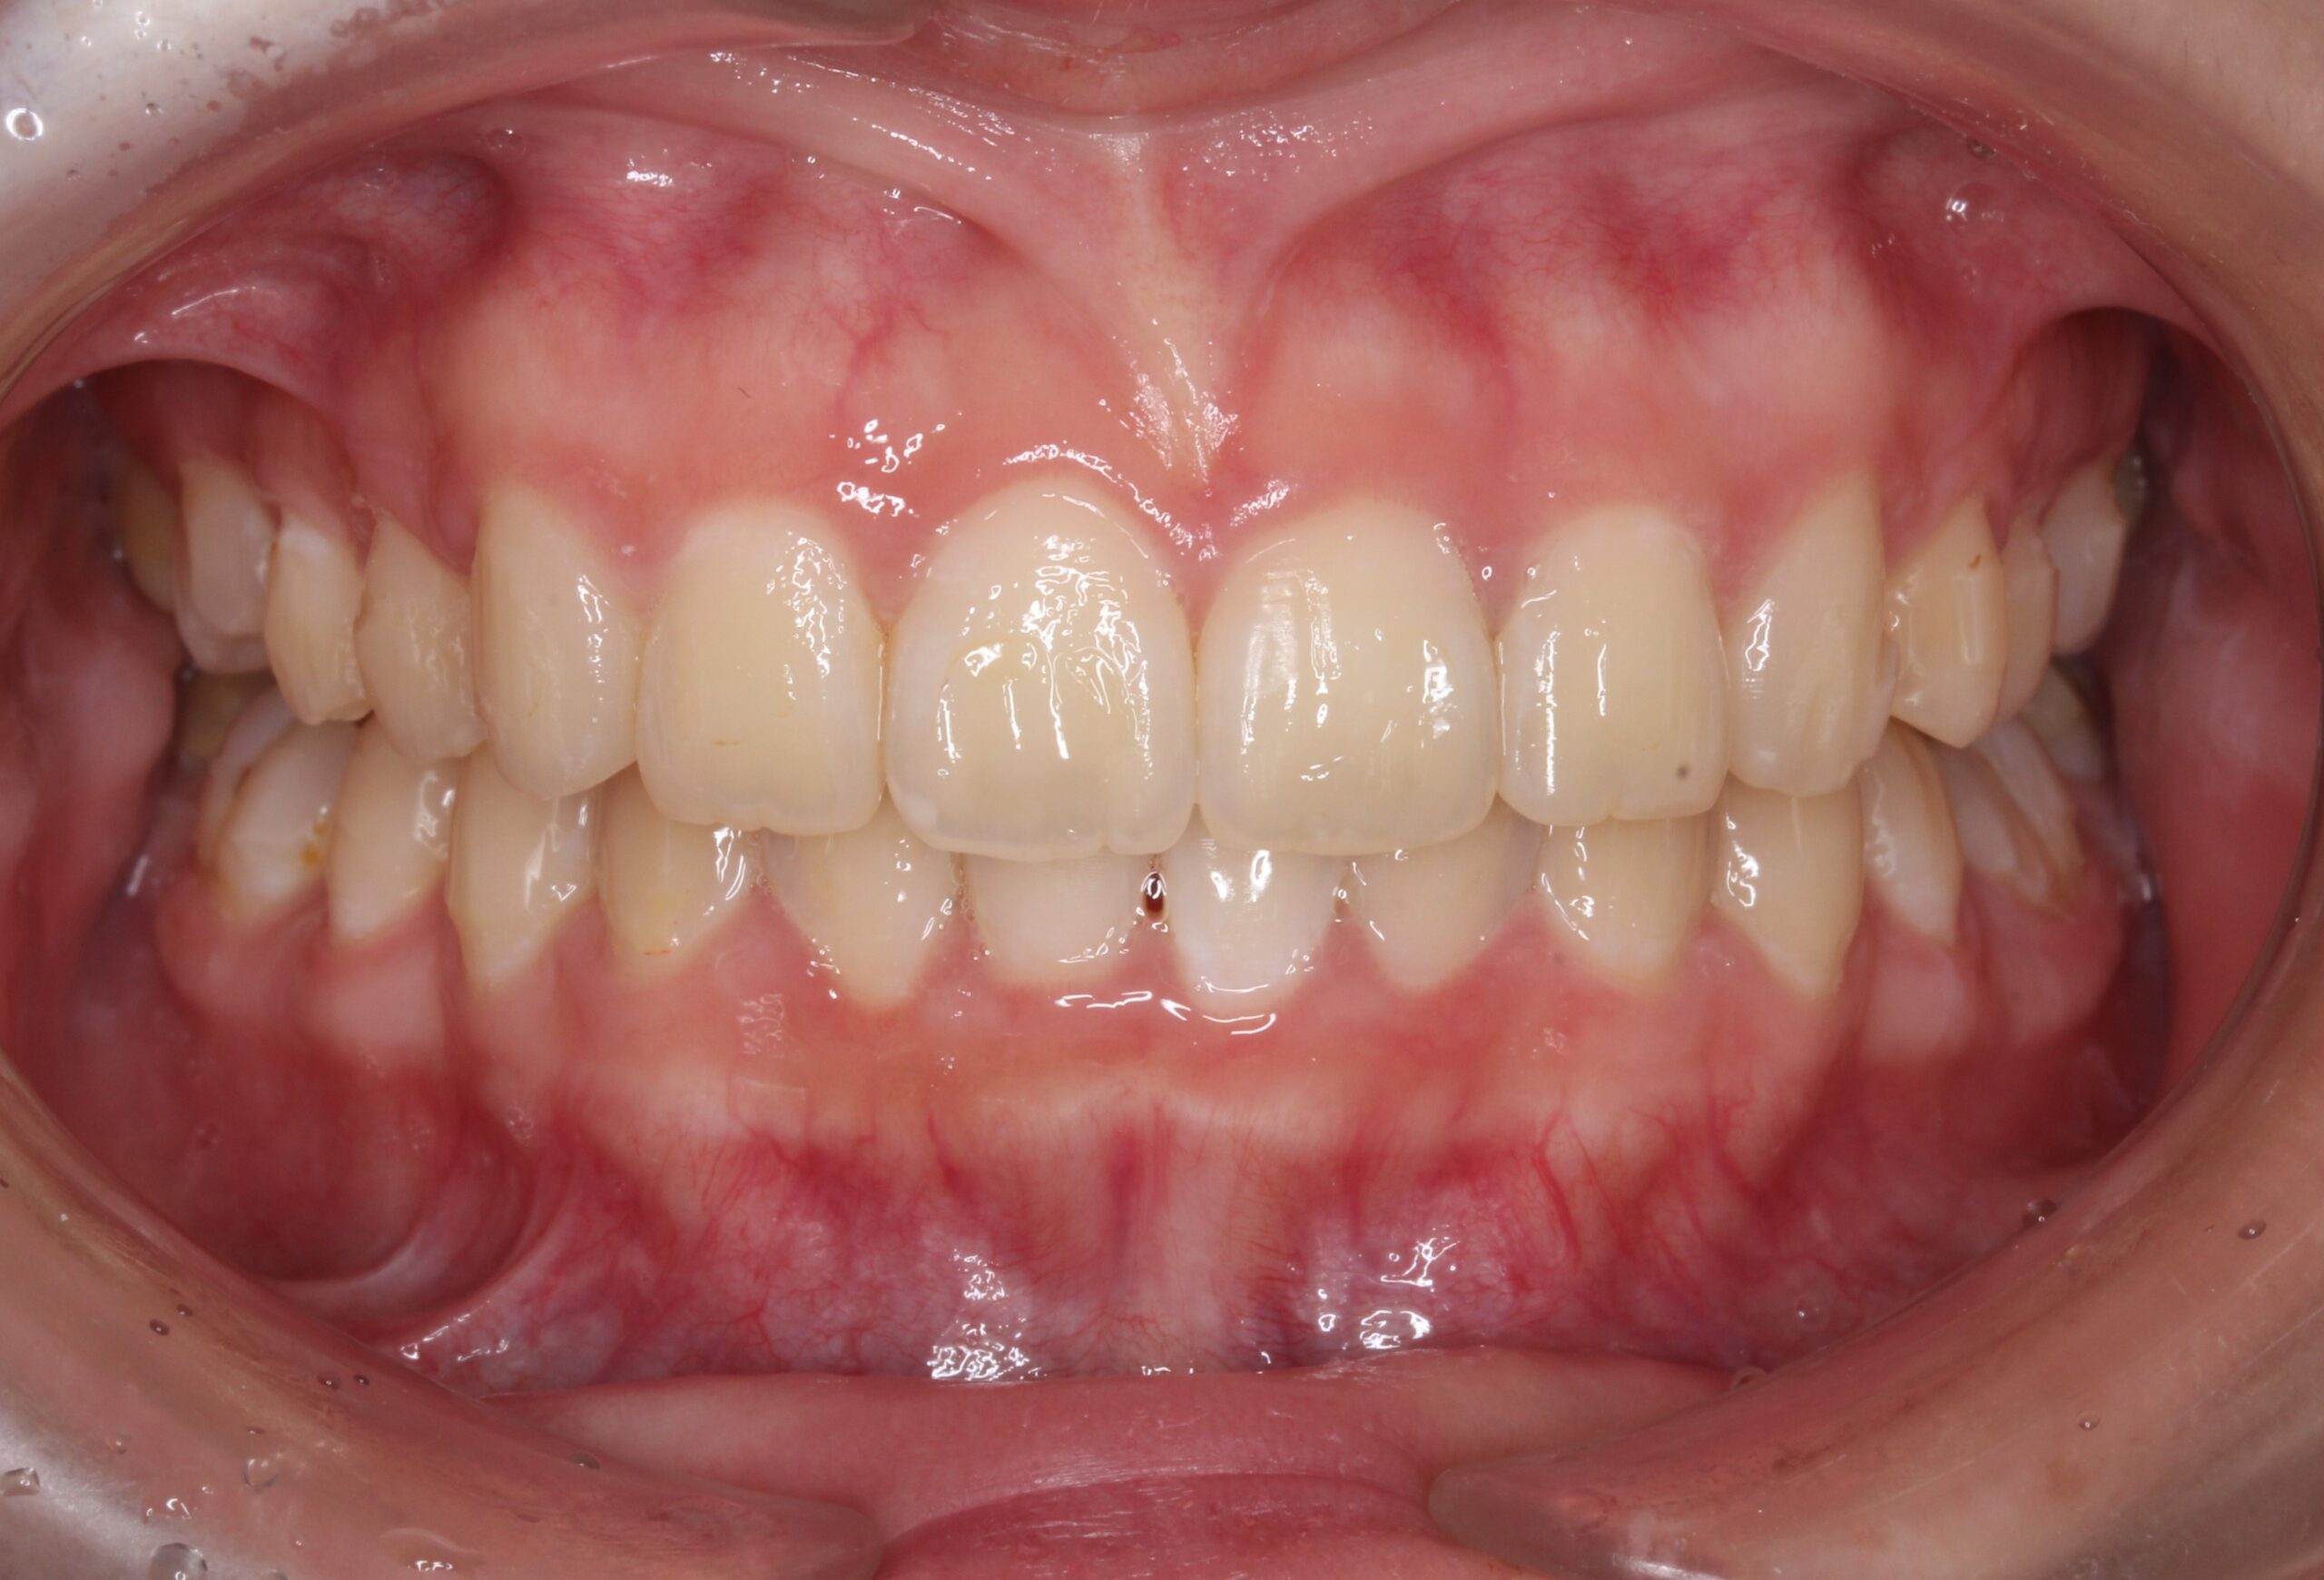

矯正術後:正面